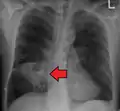

Computed tomography (CT) scan of chest showing bilateral pneumonia with abscesses, effusions, and caverns. 37-year-old male.

Lung abscesses are often on one side and single involving posterior segments of the upper lobes and the apical segments of the lower lobes as these areas are gravity dependent when lying down. Presence of air-fluid levels implies rupture into the bronchial tree or rarely growth of gas forming organism.